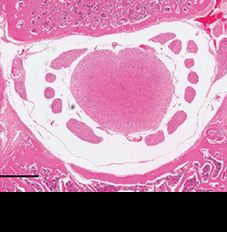

척추관 및 척수 형태 회복

척추관협착증을 유도한 쥐는 척추관이 좁아져 척수의 모양이 망가집니다.

여기에 신바로2를 투여하자 척추관과 척수의 형태가 정상에 가깝게 회복됐습니다.

정상 쥐

척추관협착증 유도 쥐

신바로2 약침 투여 쥐